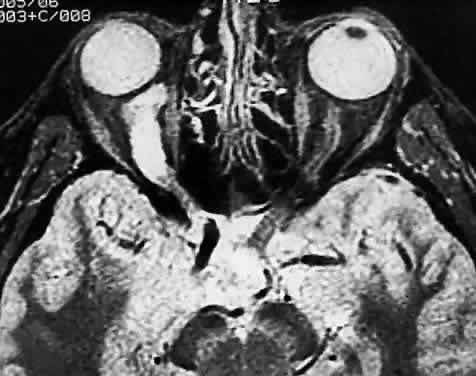

SARCOIDOSIS

The optic nerve is affected in some manner in 1% to 5% of patients with sarcoidosis and is the second most frequently involved cranial nerve—the facial nerve being the most common.67,68 Rarely, sarcoidosis may present as tumefactive enlargement of the optic nerve without evidence of systemic disease. Most cases are misdiagnosed initially as meningioma or orbital pseudotumor (Figs. 50 and 51).67,69

Fig. 50. Bilateral thickening of the optic nerve and sheaths due to sarcoidosis. Computed tomography.

Fig. 51. Sarcoidosis of the optic nerve. Noncaseating granulomas replace the optic nerve parenchyma (low power, left; high power, right).